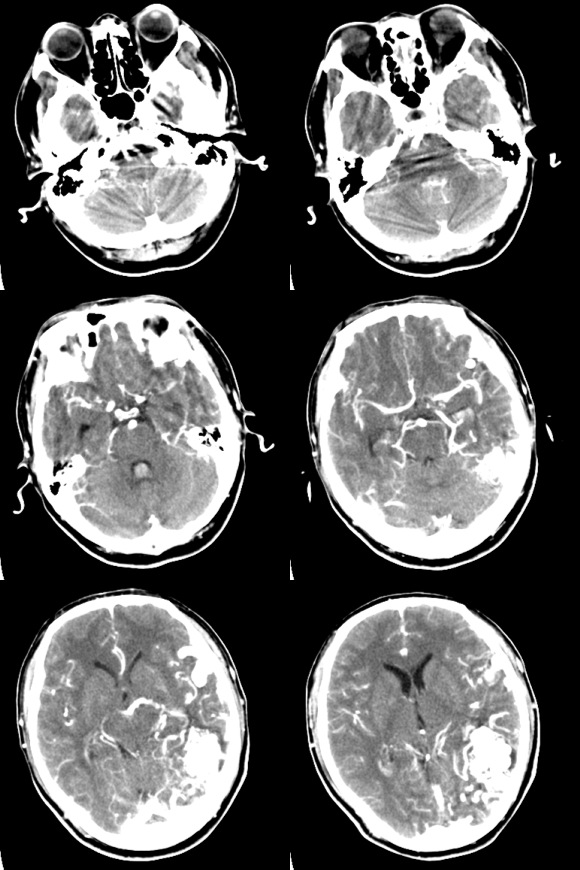

以下是引用sliucun01在2009-3-28 15:53:00的发言:[br]比较典型:脑血管畸形(avm)破裂出血破入脑室系统

以下是引用岚儿在2009-3-28 16:00:00的发言:[br]脑血管畸形(avm)破裂出血破入脑室系统.